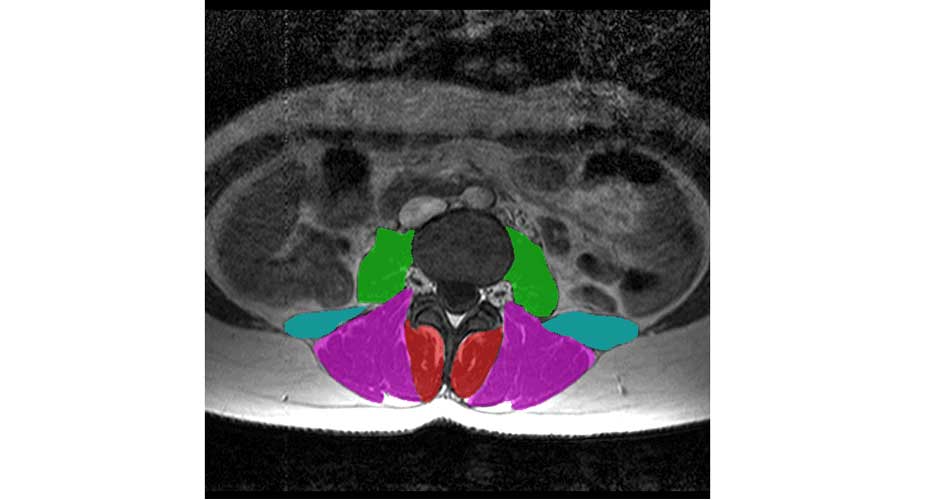

Spinal Muscle Segmentation and Characterisation

Description: Our project aims to develop computer software that can automatically assess spinal muscle size and quality from medical images. Our spine muscles are essential for controlling the movement of our upper body, allowing us to stand upright, adopt a range of postures, and lift objects from the ground. These muscles, however, are often smaller and fattier in people who have conditions such as back pain and osteoporosis. Smaller and fattier muscles indicate that the muscle has become weaker, making it less able to control the spine. However, we do not know whether muscle weakness is a symptom or a cause of these conditions. Large scale studies are required to answer this question, and these studies need suitable methods for quickly and accurately assessing muscle size and quality. Therefore, our project aims to develop computer software that can identify the spinal muscles in magnetic resonance images and then automatically calculate the muscle size and the amount and distribution of the fat within the muscle. Once we have developed our software, we will use it on images we already obtained to determine how muscle size and fat varies in people with and without osteoporosis.